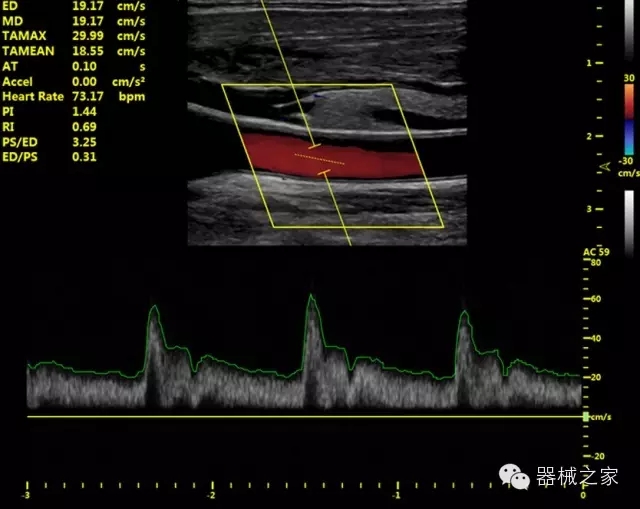

臨床圖片賞析